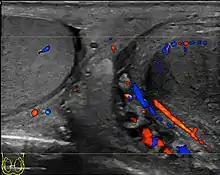

- Ultrasound scanning

- Lefort C, Thoumas D, Badachi Y, et al. (July 2001). "Orchites ischémiques: À propos de 5 cas diagnostiqués en écho-Doppler couleur" [Ischemic orchiditis: review of 5 cases diagnosed by color Doppler ultrasonography]. Journal de Radiologie (in French). 82 (7): 839–42. PMID 11507447. INIST:1080037.